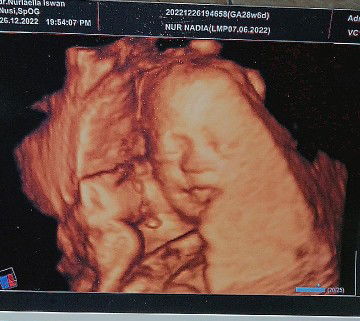

apa boleh hamil 4w minum ice crem?

Menantikan saat menjadi ibu